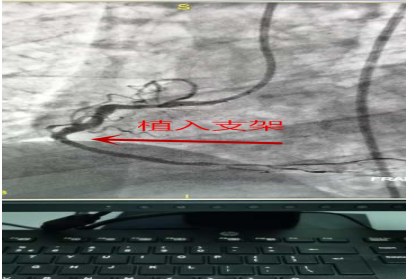

患者杨某某,男,66岁,农民,于2020年03月22日11:40因“发作性胸痛7天”入院。患者于入院前7天(16日10时左右)在劳动时出现胸痛不适,主要为左侧胸部钝痛不适,感轻微压榨感,向背部、左肩及左臂内侧放射,伴心悸不适,持续时间约10-15分钟,患者休息后逐渐缓解;20日7时左右患者再发胸痛一次,与16日相似,但持续时间延长,约30分钟,同日再行发作一次;患者院外未行正规诊治,现无明确胸痛不适。入院后考虑急性非ST抬高 心肌梗死,择期行PCI治疗。患者于2020.03.24 11时在导管室行PCI治疗,手术约50分钟,成功行球囊扩张和支架植入,患者平安返回病房,胸痛缓解。

术后效果: